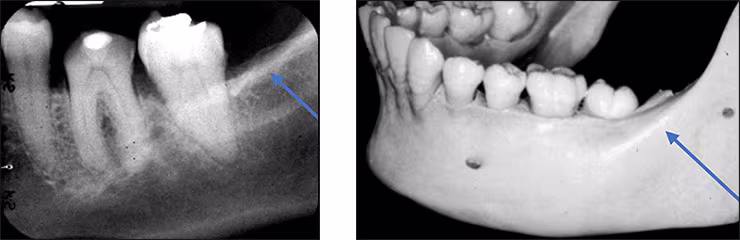

Mandibular canal – The mandibular canal is the pathway in bone where the inferior alveolar nerve and blood vessels course through the mandible. The canal extends from the mandibular foramen within the ramus anteriorly to the mental foramen. This tubular bilateral radiolucency often demonstrates fine radiopaque boundaries. The mandibular canal is recorded on mandibular premolar and molar periapical images. It is also referred to as the inferior alveolar nerve canal. The mandibular foramen is not recorded on mandibular periapical images.